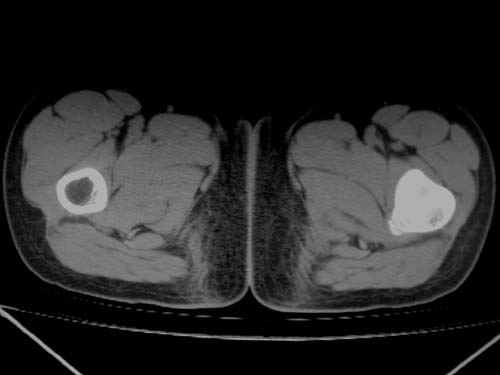

标题: CT19608:女12岁,左髋部疼痛,无发热病史 [打印本页]

标题: CT19608:女12岁,左髋部疼痛,无发热病史

左股骨干增粗,磨玻璃样改变——考虑骨纤维异常增殖症!

左股骨干增粗,磨玻璃样改变——考虑骨纤维异常增殖症!骨化性纤维瘤?